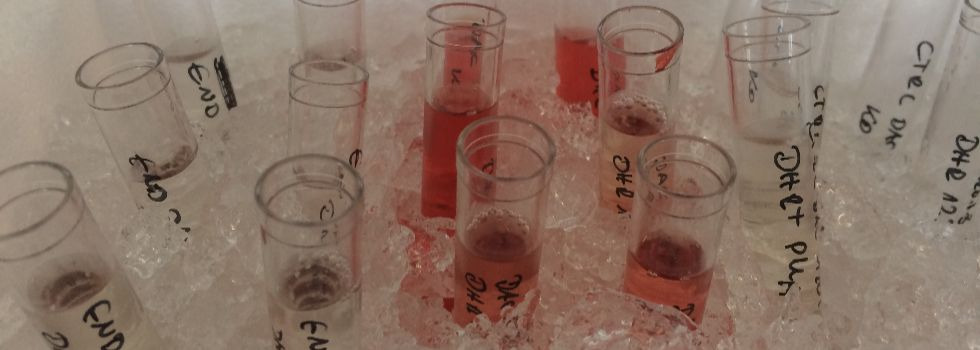

1. Cardiovascular tissue engineering

2. Cardiovascular inflammatory research

Cardiovascular Tissue Engineering